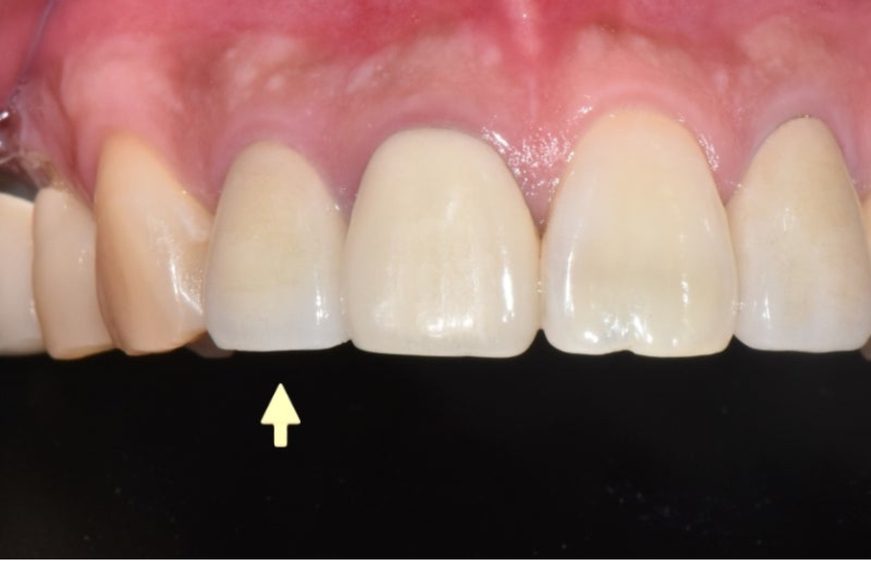

▲Cứu chân răng bằng phẫu thuật kéo răng

Nếu một chiếc răng bị gãy và phần

chân răng còn lại còn đủ dài thì

có thể phẫu thuật kéo ra một phần

và giữ lại phần chân răng còn lại.

▲ Gắn lại mão răng sau phẫu thuật kéo răng